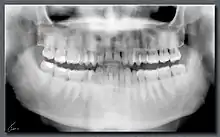

Ortopantomografía

La ortopantomografía o radiografía panorámica es una técnica radiológica que representa, en una única película, una imagen general de los maxilares, la mandíbula y los dientes. Por tanto, es de primordial utilidad en el área dentomaxilomandibular.